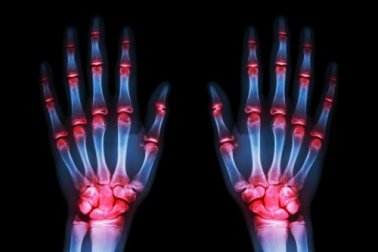

- L’arthrose touche le plus fréquemment les mains, dans 70% des cas.

- Comme nous le savons déjà, lorsque nous allons chez le médecin pour trouver de l’aide, c’est que nous n’en pouvons plus. Les douleurs dans les mains sont terribles, elles nous empêchent de dormir la nuit et nous souffrons déjà de petites déformations.